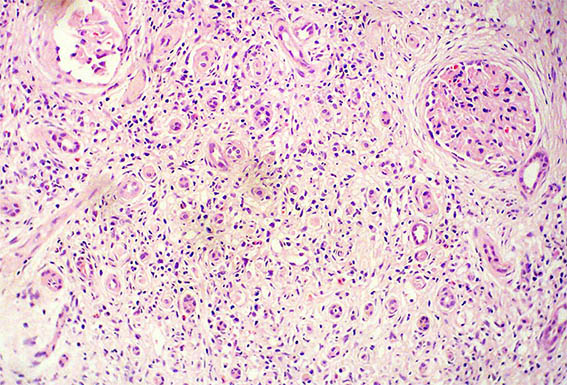

Figure 1. H&E, X100. Note the prominent tubulointerstitial involvement.